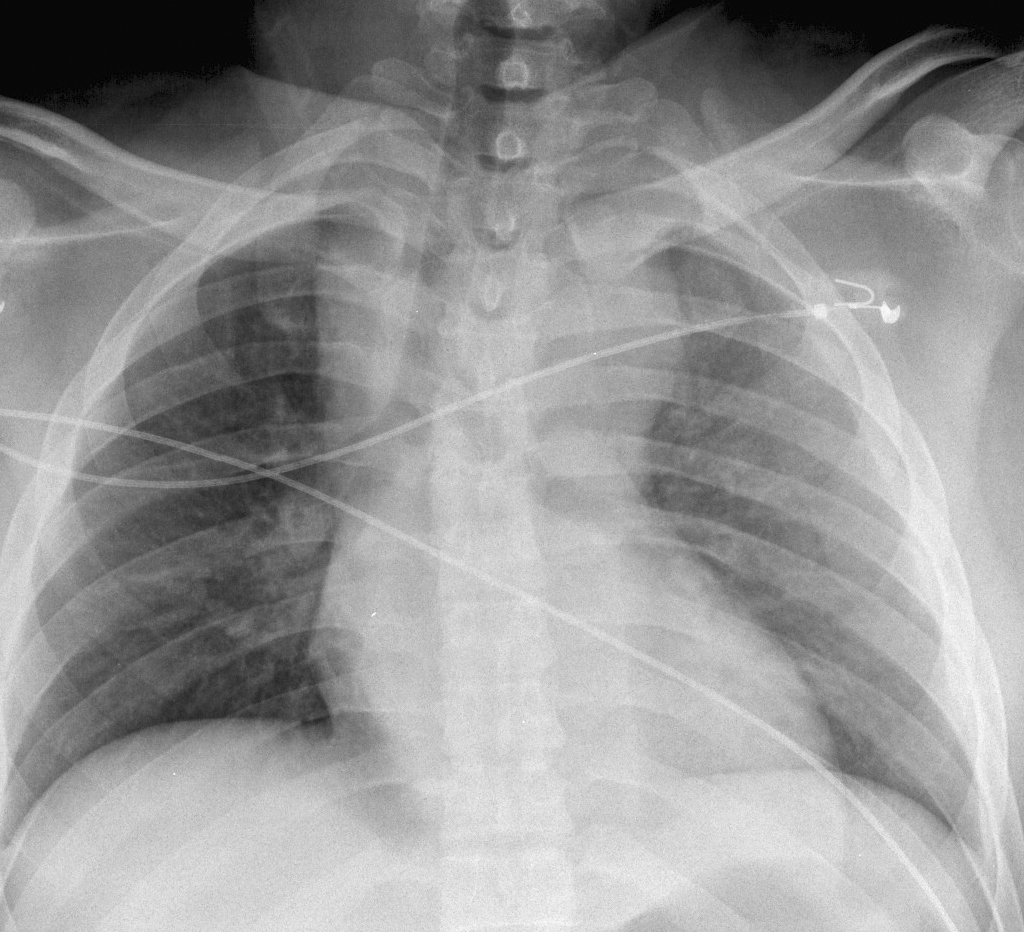

Gallery Blunt Chest Trauma Spine trauma Case 7a

Case 7a